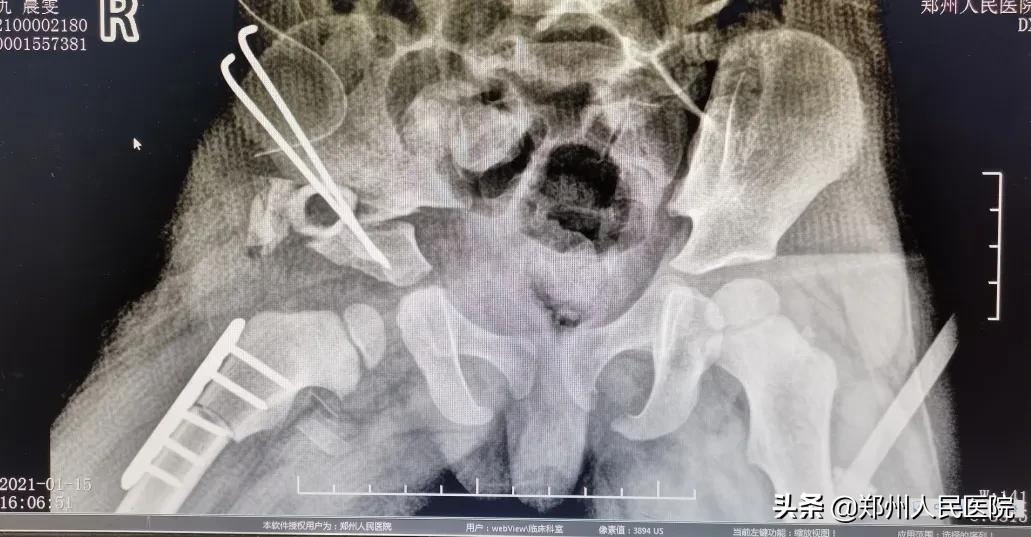

术前

“患者的情况已经不适合截骨手术,也就是保髋治疗。需要进行髋关节置换,放进一个人工的髋臼杯,再将股骨颈、磨坏的股骨头截掉,换上人工的股骨柄和股骨头,这样就形成了一个新的人工髋关节。通过手术可以解除患者髋关节的疼痛、改善走路一瘸一拐的症状。”尹万乐主任医师告诉小编。